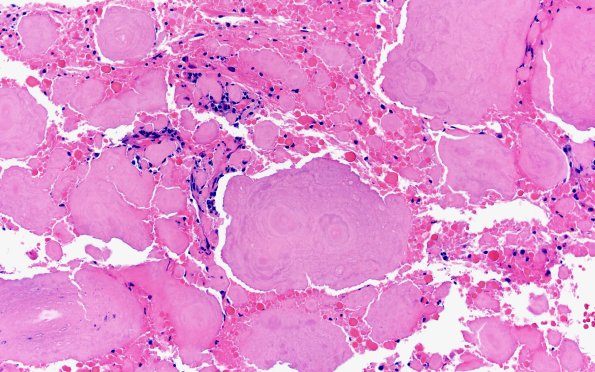

7B2 Amyloidoma (Case 7) H&E 10X

7B2,3 Higher magnification of the amorphous aggregates shows concentric rings. (H&E)